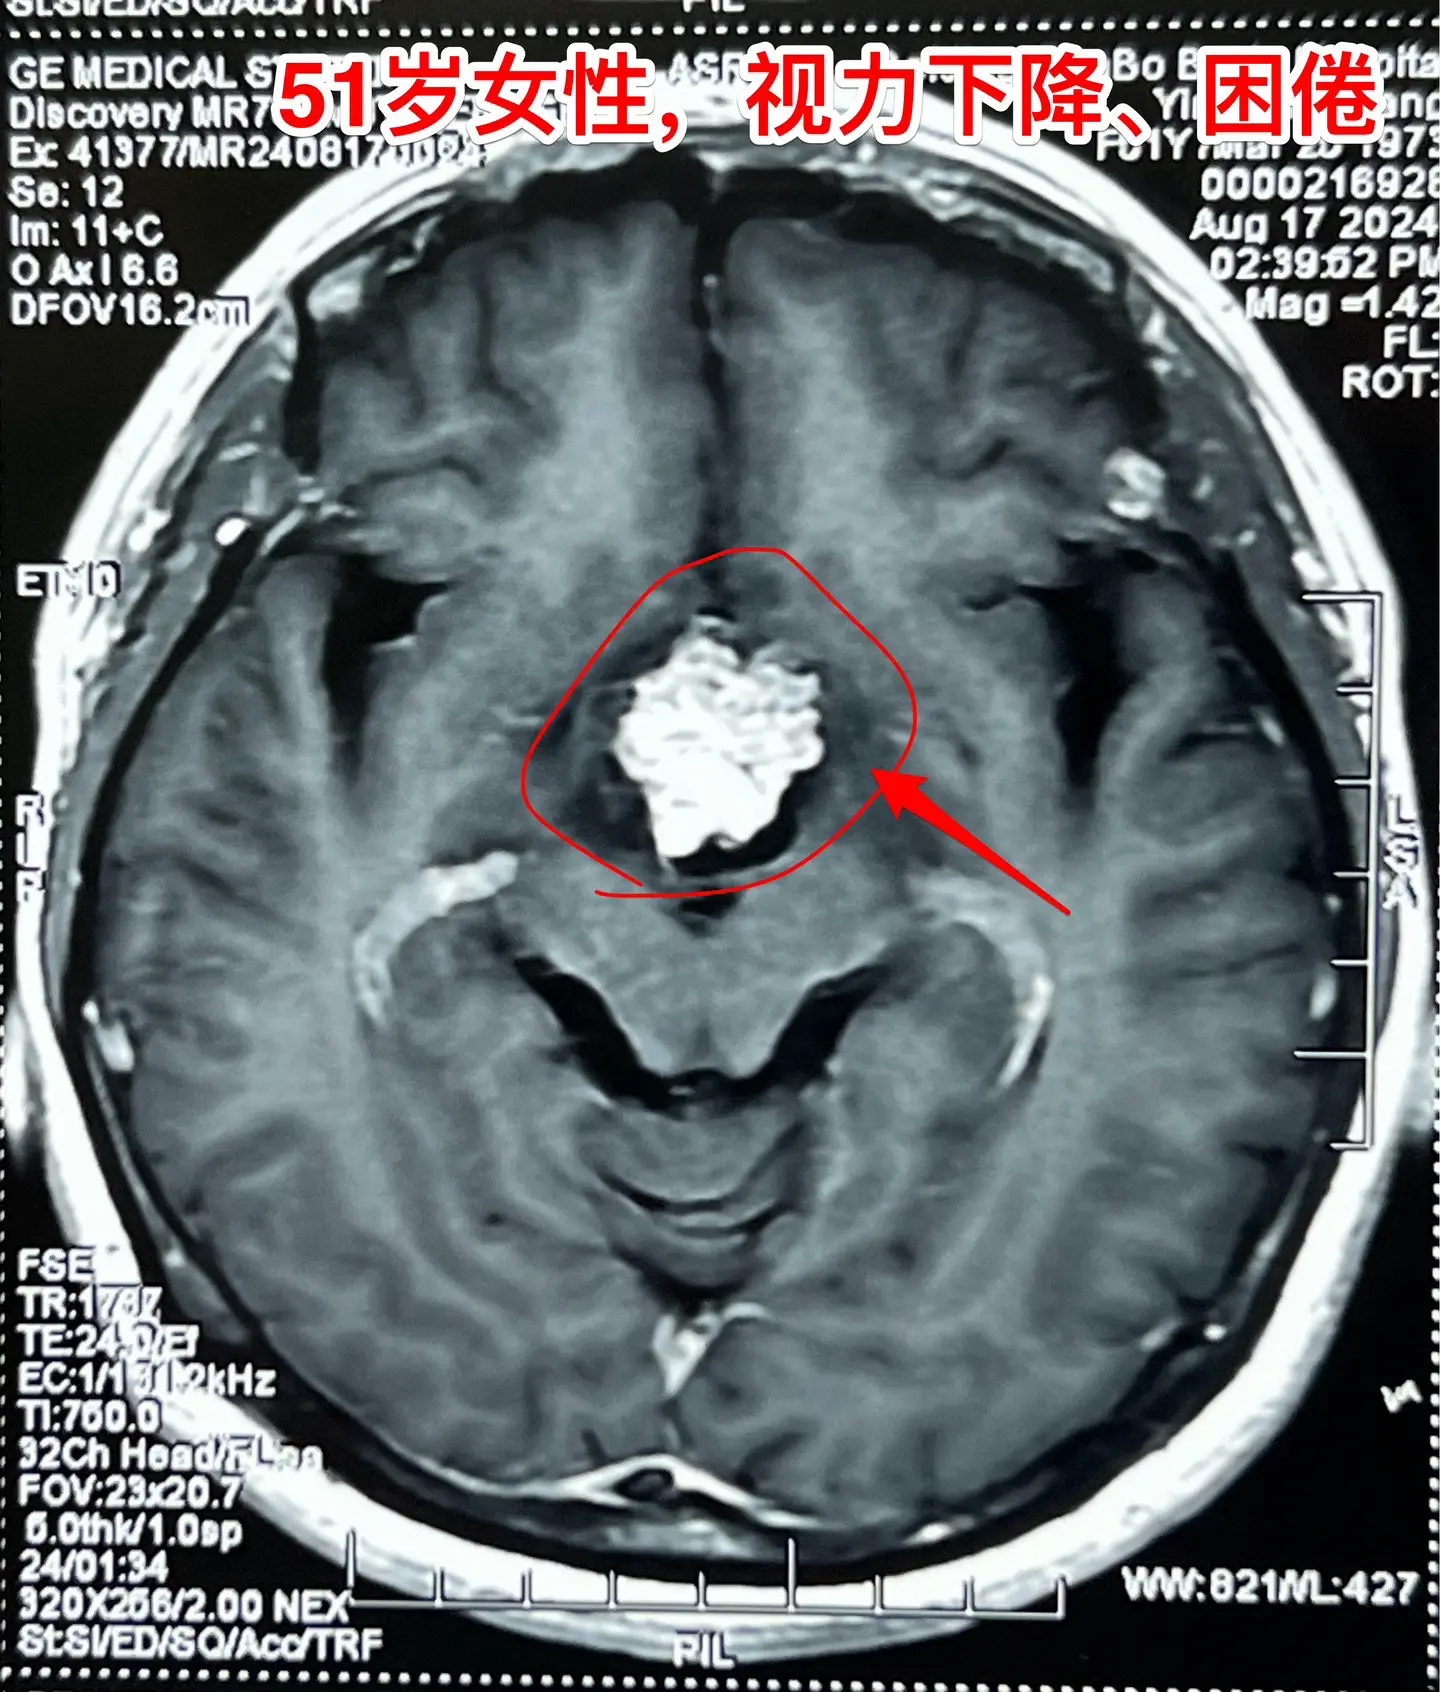

视频中展示出来的是第一个和第三个病人的影像学资料。

第一个病人女性,51岁,山东人。患者的弟弟就是神经外科医生。病人因为视力下降、困倦、无精打采到医院检查发现颅咽管瘤,是乳头型颅咽管瘤。患者家人一致要求作开颅手术切除颅咽管瘤。今天的手术很顺利,颅咽管瘤得到完全切除,晚上病人作完了CT就从ICU转到普通病房了。